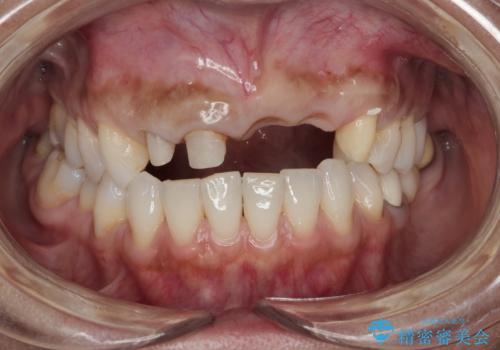

- 前歯がグラグラし、においもする、とのことで改善を求めて来院されました。

一見して問題ないように見える左側の2前歯は、セラミックを除去してみると亀裂や虫歯の再発が見られました。

抜歯時に可及的に歯肉のボリュームを保つよう骨充填材とコラーゲン製剤による填塞を行い審美的かつ機能的なブリッジとなるよう治療を進めます。

一件綺麗に見えるセラミックも適合や精度が悪いと、内部で虫歯が進行し亀裂や破折、悪臭の原因となることがあります。